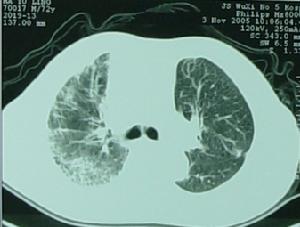

2.復發性細菌性肺炎反覆發作時可以造成支氣管擴張,早期這種支氣管擴張可呈圓柱形並且是可逆鵻的但在多次肺炎發作後由於支氣管損害可發展成靜脈曲張狀或囊性支氣管擴張位於下葉是其特點,感染早期胸片是正常的,在肺底有線狀陰影聚集這時支氣管造影可顯示支氣管擴張當支氣管擴張進鵻一步發展則可呈小囊狀支氣管擴張,用高解析度CT(HRCT)可取代支氣管造影而獲得診斷。

大部分病灶纖維化4、糖皮質激素:短期口服似乎能改善肺功能,但副作用明顯。可用於ABPA。